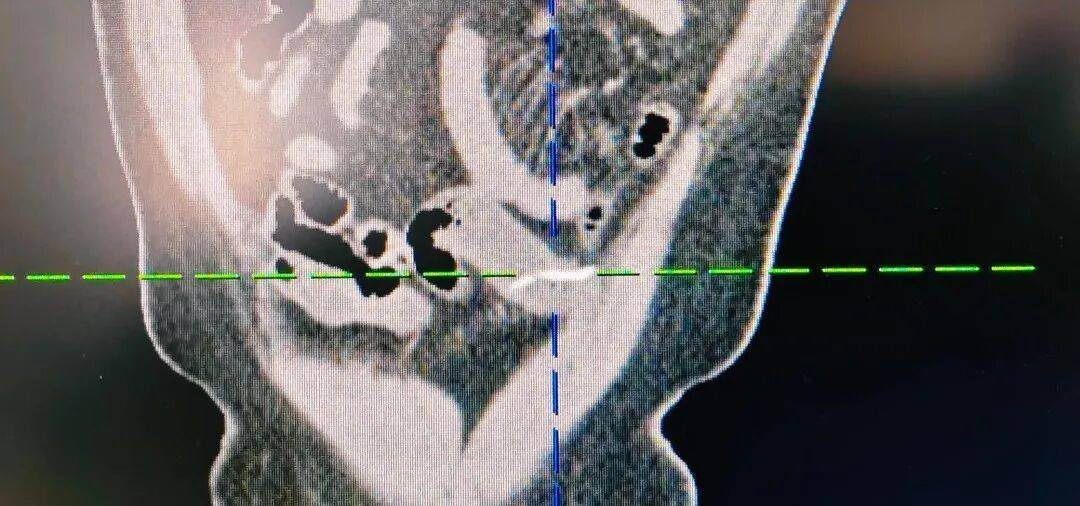

经漳州第三医院普外二科团队详细检查,最终确诊为小肠异物穿孔,而闯下弥天大祸的,竟然是一根不起眼、只有两三公分长的小鱼刺,普外二科团队为患者行“腹腔镜下小肠破裂修补+异物取出术”。